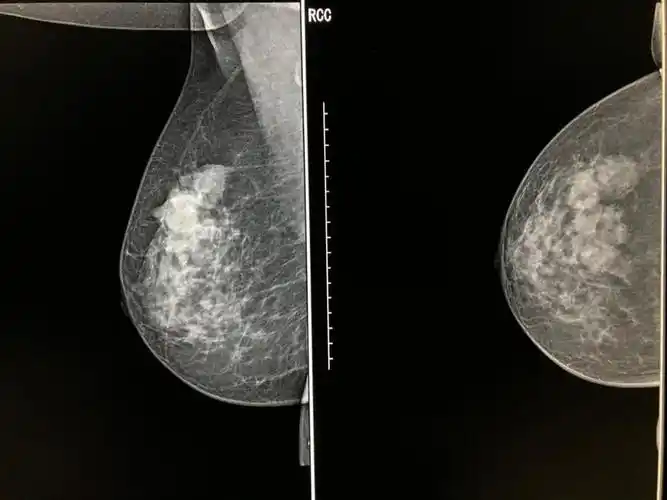

相关图片